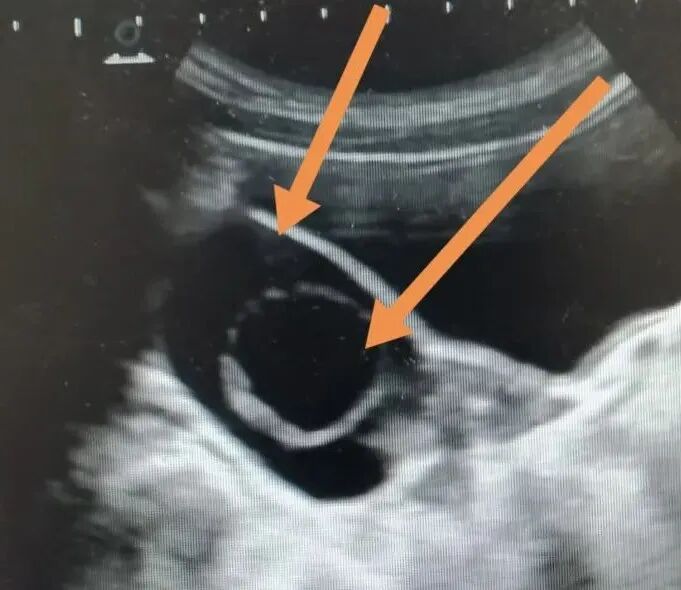

結(jié)果顯示:1.孩子的骨齡約9歲,符合她的年齡和身高;2.孩子的性激素水平仍處于低水平狀態(tài);3.孩子的彩超顯示右側(cè)附件區(qū)可見一個大小約60*45*42mm的囊性包塊,形狀呈橢圓形,內(nèi)透聲好;內(nèi)另可見一個大小約31*30mm的囊性回聲。

好家伙,居然“囊中囊”!原來,孩子并不是真的來“月經(jīng)”,陰道血性分泌物是右側(cè)卵巢囊腫導(dǎo)致的。

首次就診檢查時發(fā)現(xiàn)“囊中囊”